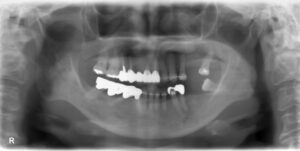

上下顎3本欠損症例

BEFORE AFTER 59歳女性/上下顎3本欠損/インプラント埋込手術 【治療内容】 左下の第一大臼歯、第二大臼歯は…